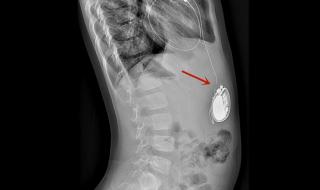

男子植入最小人工心脏